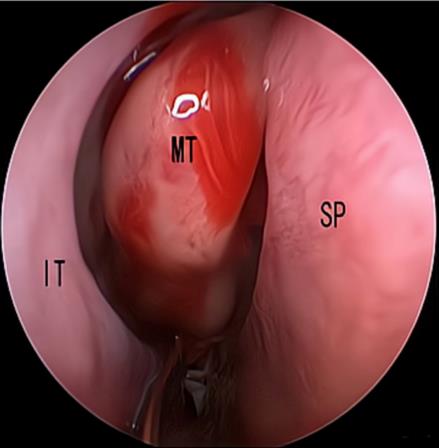

摘要:目的 探究经中鼻甲基板入路的手术技巧及临床效果,旨在系统评估一种兼具良好手术视野和微创性的蝶窦开放径路。方法 回顾性分析2019年9月-2023年9月该院收治的35例孤立性蝶窦病变或单侧蝶窦伴毗邻筛窦受累患者的临床资料,均经中鼻甲基板入路的“四步”程序化操作开放蝶窦。观察手术相关情况和并发症发生情况;采用视觉模拟评分法(VAS)评分,评估头痛和流涕等症状改善情况;采用改良隆德-肯尼迪(MLK)评分,评价术腔恢复状况。结果 所有患者术中保留钩突、中鼻甲和筛泡,26例(74.3%)保留上鼻甲;所有患者均达到临床治愈标准,表现为:术腔引流通畅,黏膜完全上皮化,以及蝶窦开口维持良好开放状态。术后病理显示:蝶窦霉菌病19例(54.3%),蝶窦息肉7例(20.0%),蝶窦黏膜慢性炎症9例(25.7%)。所有患者均未发生严重并发症,仅1例(2.9%)于术后12 d出现中鼻甲创面渗血,经电凝止血后治愈。头痛VAS评分由术前的(4.71±1.66)分,降至术后的(0.83±0.39)分,手术前后比较,差异有统计学意义(t = 13.71,P < 0.01);流涕VAS评分由术前的4.00(0.00,6.00)分,降至术后的0.00(0.00,1.00)分,手术前后比较,差异有统计学意义(Z = -4.47,P < 0.01);手术前后嗅觉减退VAS评分比较,差异无统计学意义(P > 0.05)。MLK评分由术前的4.50(2.00,4.00)分降至1.00(0.00,1.00)分,手术前后比较,差异有统计学意义(Z = -5.20,P < 0.01)。结论 经中鼻甲基板入路蝶窦开放术,严格遵循鼻窦解剖层次,在最大限度地保留鼻腔生理结构的前提下,可获得理想的术野暴露。该术式对于局限于蝶窦及后组筛窦的病变,具有确切的临床疗效。值得应用于临床。